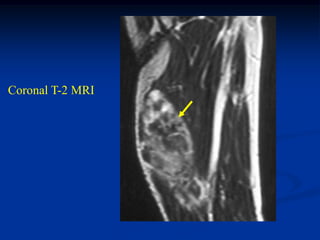

Case #255.1

Axial T-1

35 yr female with

slightly tender lump

below tip of scapula

T-2

for 1 yr

Gad

Cor T-1   T-2   Gad